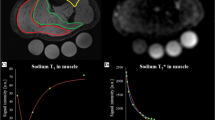

The calves of seven healthy subjects underwent imaging pre- and post-exercise via 7 T 23Na MRI (3D fast low angle shot, TR/TE = 80 ms/0.160 ms, 4 mm × 4 mm × 4 mm) and 1 week later by 1H MRI (multiple spin-echo sequence, TR/TE = 3,000 ms/15–90 ms). Four type 2 diabetics also participated in the 23Na MRI protocol. Pre- and post-exercise sodium signal intensity (SI) and proton T2 relaxation values were measured/calculated for soleus (S), gastrocnemius (G), and a control, tibialis anterior (TA). Two-tailed t tests were performed.

In S/G in healthy subjects post-exercise, sodium SI increased 8–13% (p < 0.03), then decreased (t 1/2 = 22 min), and 1H T2 values increased 12–17% (p < 0.03), then decreased (t 1/2 = 12–15 min). In TA, no significant changes in sodium SI or 1H T2 values were seen (−2.4 to 1%, p > 0.17). In S/G in diabetics, sodium SI increased 10–11% (p < 0.04), then decreased (t 1/2 = 27–37 min) without significant change in the TA SI (−3.6%, p = 0.066).